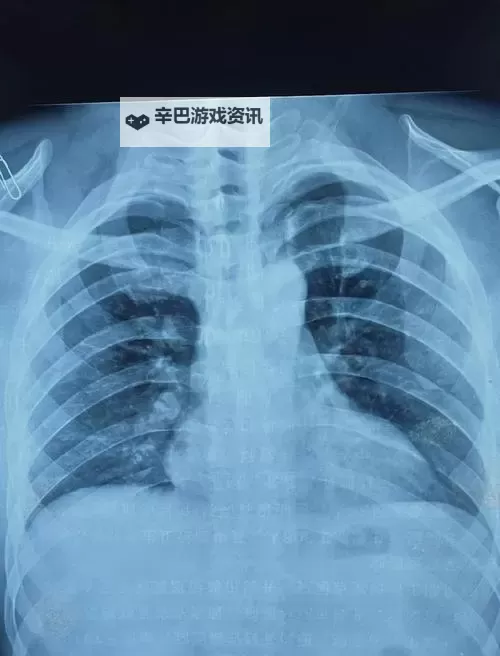

首先,胸片作为一种常见的医学影像检查手段,主要用于筛查肺部疾病、胸腔疾病以及监测某些慢性疾病的治疗效果。在医学界,胸片的作用不可忽视,它不仅可以帮助医生早期发现潜在的疾病,还能为治疗方案的制定提供重要依据。随着技术的发展,数字化、多层次的影像处理手段不断升级,使得胸片的诊断准确性大大提高,也使得医学研究得以深入。因此,关于胸片的最新动态,尤其是一些创新的技术应用,成为业内外关注的焦点。

在一些医疗平台或专业论坛上,时常会有“胸片曝光”或“最新胸片研究”的报道被大量转发。这些内容可能包括疑难病例的影像展示、新型筛查技术的应用、以及在早期筛查中取得的突破。据报道,通过高分辨率的胸片及人工智能辅助诊断系统,早期肺癌的检测率明显提升,使得患者可以在疾病尚处于早期时得到诊断和治疗。这些“猛料”无疑为公众带来了希望,也让人们对未来的医学影像检测充满期待。